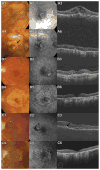

Figures